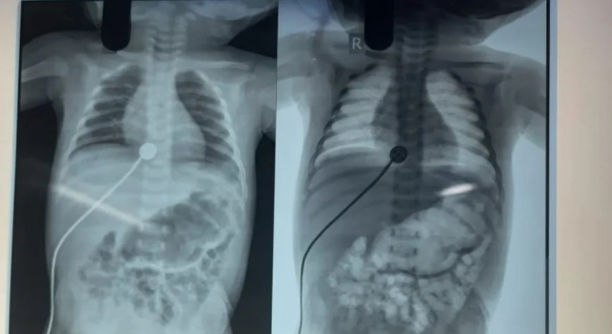

Abdominal X-rays (showing dilated bowel loops)

Meconium Ileus is a bowel obstruction in newborns caused by thick, sticky meconium (the baby’s first stool) blocking the small intestine, typically the ileum. It is often the first sign of cystic fibrosis (CF) and requires prompt treatment to avoid complications like bowel perforation or infection.

No passage of meconium within the first 24–48 hours after birth

Abdominal distension (swollen belly)

Vomiting, often greenish (bilious)